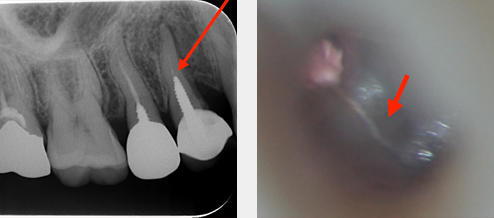

その代表的なものが、「根管治療」(歯根内部の神経の治療)です。

根管内部は「見えないもの」とされていて、手探りで治療をするしかありませんでした。しかし、マイクロスコープの出現によって最大24倍という高倍率の視野がもたらされるようになりました。

右の写真のように、根管は非常に複雑な形態を呈しております。(おおよそですが、歯全体の長さは2cm、幅は1cmで、根管の太さは1mm以下です。)

歯の寿命に大きく関わる根管治療の成績を高めるにあたって、マイクロスコープは欠かせないものとなっております。

歯根の形態がまっすぐであれば、根尖孔(根っこの先)まで確認できます。(24倍拡大率の視野)

マイクロルーぺの項目にある8倍拡大率の視野よりも、さらに明るく鮮明に歯の内部が見えます。

マイクロスコープによる診断

裸眼では確認できない歯のひび割れや虫歯を確認することができます。

マイクロスコープによる治療

裸眼では難しい処置が可能になることで、治療後の予知性を高めることにつながります。

〔例:根管内の破折器具の除去〕